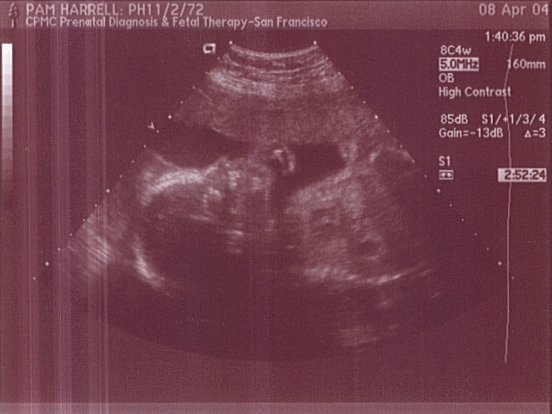

This is a profile shot of baby Harrell. Facial bones are more developed. This was taken on April 8, 2004.